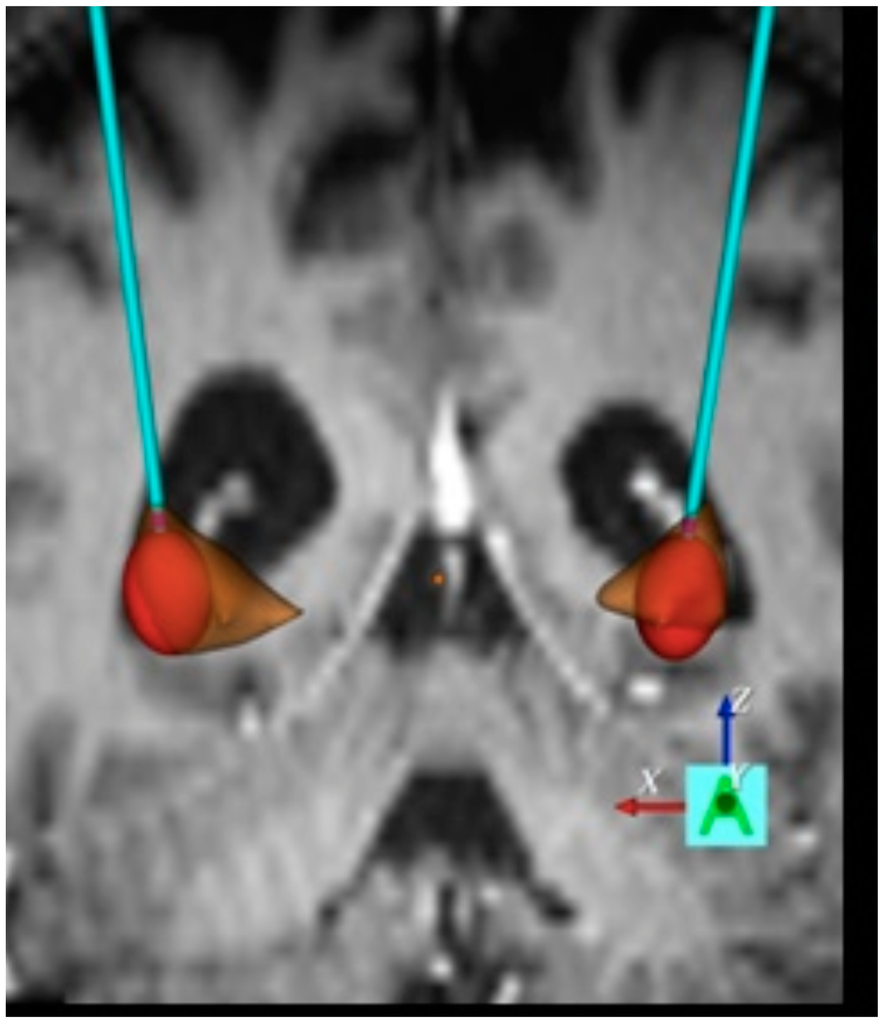

- Wojtecki, L.; Groiss, S.J.; Ferrea, S.; Elben, S.; Hartmann, C.J.; Dunnett, S.B.; Rosser, A.; Saft, C.; Sudmeyer, M.; Ohmann, C.; et al. A prospective pilot trial for pallidal deep brain stimulation in Huntington’s disease. Front. Neurol. 2015, 6, 177. [Google Scholar] [CrossRef] [PubMed]